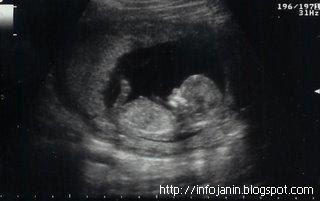

Bayi sudah bisa mengedipkan matanya selain itu retina matanya telah mulai terbentuk. Aktifitas otaknya yang berkaitan dengan pendengarannya dan pengelihatannya sudah berfungsi, bunda dapat memulai memperdengarkan lagu yang ringan dan mencoba untuk memberi cahaya lebih disekitar perut, mungkin bunda akan merasakan anggukan kepala si kecil. Berat badan bayi sudah mencapai 750-780gram, sedangkan tingginya 35-38 cm.